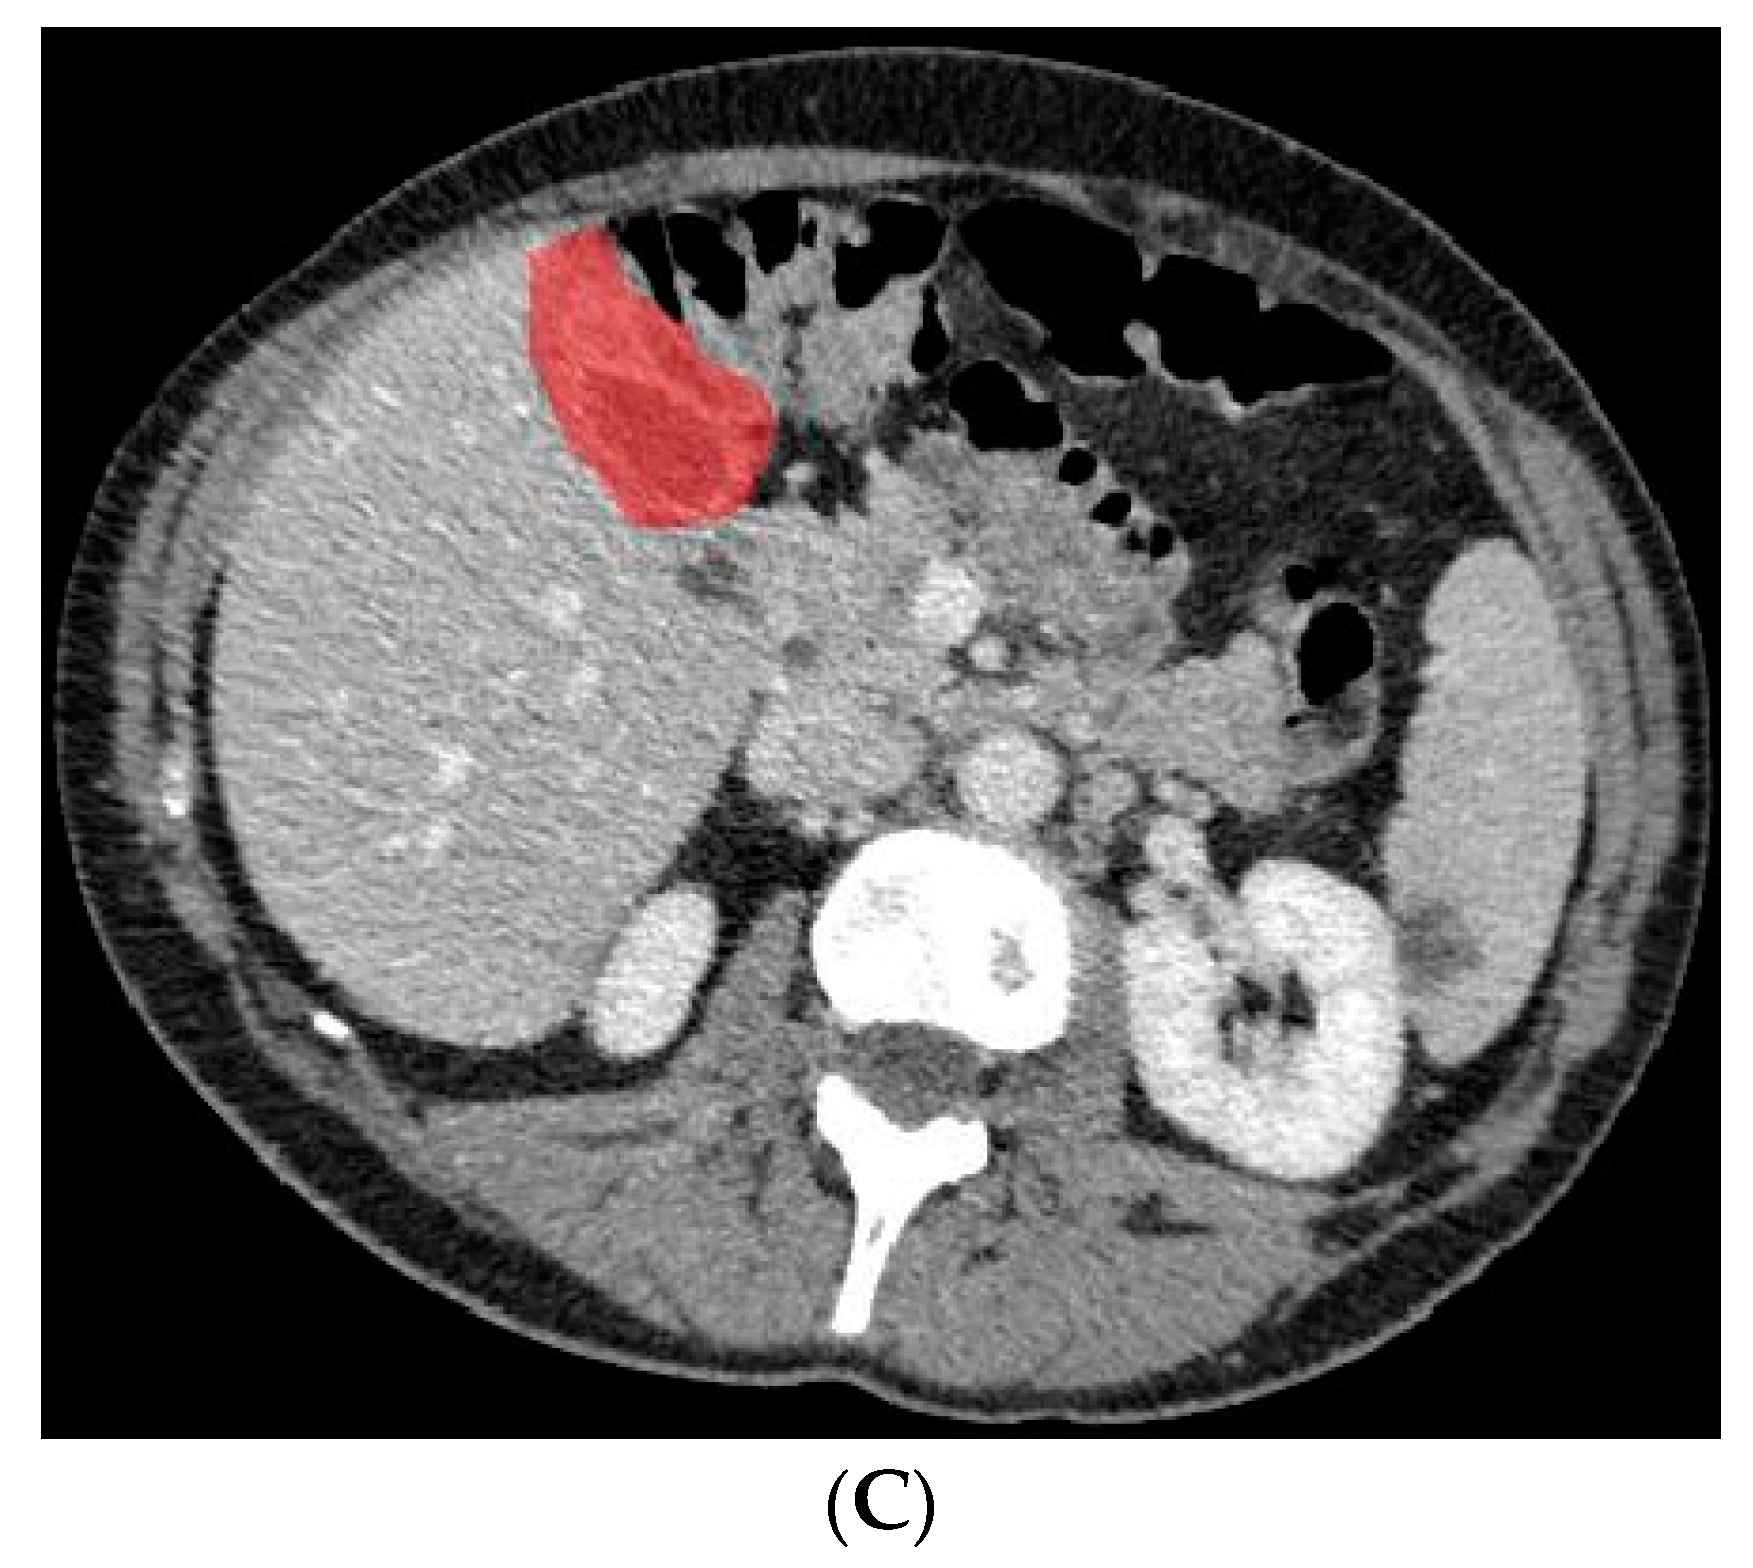

In a previous study, the suspicion of invasion of adjacent liver parenchyma was observed to be positively related to GBC [5]. Therefore, in addition to using only the gallbladder on CT images when training the deep learning model, a separate analysis was performed to investigate whether the combination of the gallbladder and adjacent liver parenchyma could increase the performance of the deep learning model when differentiating between GBC and benign gallbladder disease. The segmentation of a 2 cm rim of liver parenchyma adjacent to the gallbladder was automatically generated and adjusted by an experienced abdominal radiologist if necessary. The adjacent liver parenchyma was combined with the segmented gallbladder as training data for the deep learning model. Figure 4 shows examples of input CT images with segmentation of both the gallbladder and 2 cm of adjacent liver parenchyma. The deep learning model based on the combination of the gallbladder and adjacent liver parenchyma was trained and tested by the same methodology as described for the model solely based on the gallbladder.